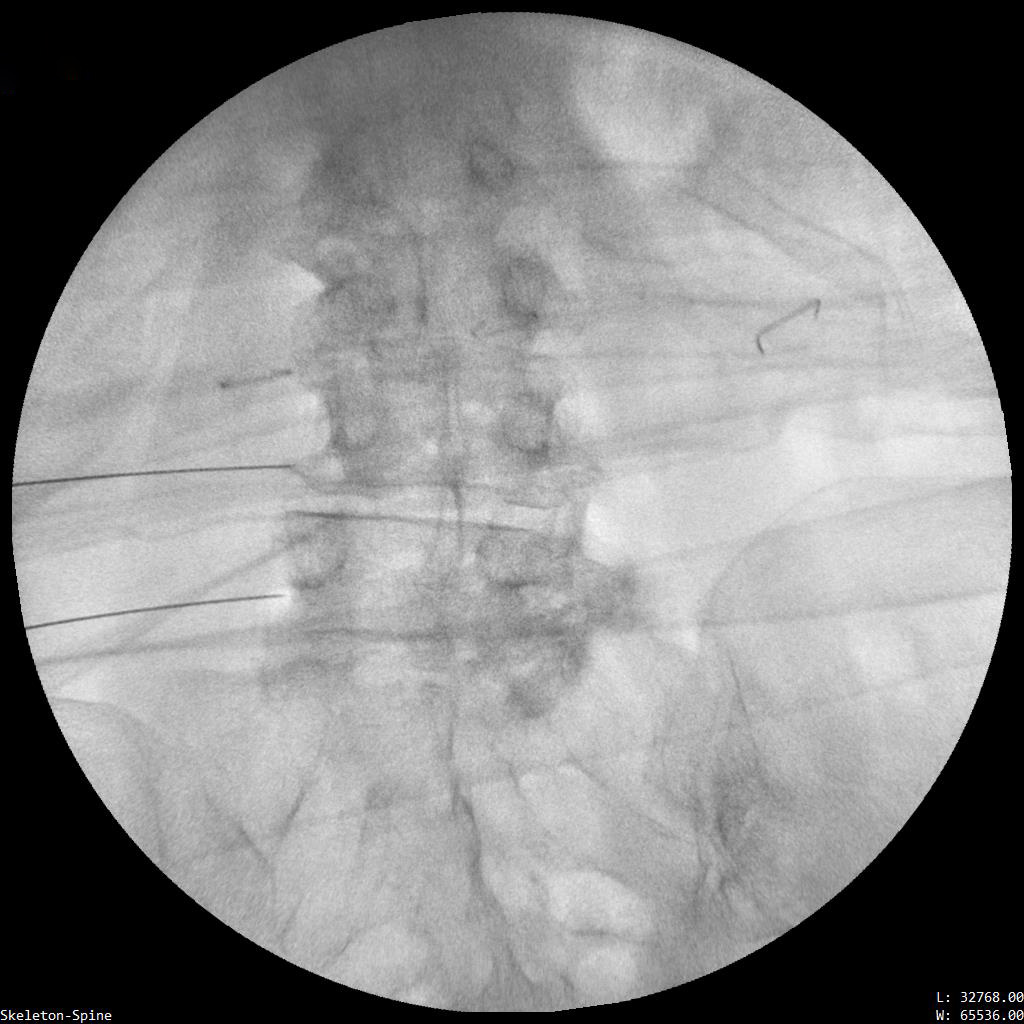

Ασθενής με σπονδυλαρθρίτιδα και 2 δισκοκήλες

Ασθενής 86 ετών με έντονο άλγος οσφύος, αντανάκλαση στο κάτω άκρο και αιμωδίες αριστερού άκρου ποδός απο 2μήνου λόγω σπονδυλαρθρίτιδας και 2 δισκοκηλών σε 2 επίπεδα. Με τοπική αναισθησία τοποθέτηση 2 βελόνων.  Έλεγχος σωστής τοποθέτησης με χρήση σκιαστικού και εισαγωγή μείγματος αναλγητικών. Άμεση ανακούφιση με αποτέλεσμα που διατηρείται 1.5 χρόνο μετά.